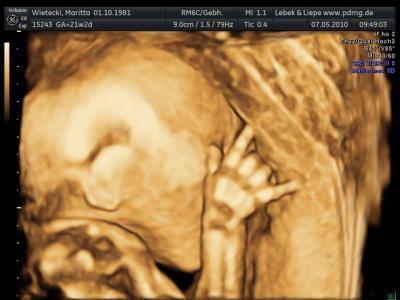

Mein Menne ist ja dem Tauch-hobby verfallen und ich bin eher eine Rock´n´roll Mieze,als wir damals erfahren hatten,das wir schwanger sind,da kam immer nur der Spruch, es wird ein Taucher, ich hab immer abgestritten und sagte,der Kleine wird den Rock´n´roll im Blut haben und nun schaut mal,wie sich der Kleine bei der Feindiagnostik schon vor einigen Monaten dazu äußerte....

Bild zu Mal was zum schmunzeln!!! - Forum für September - Mamis